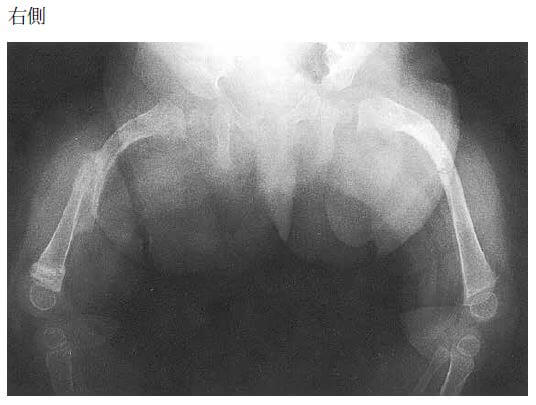

問題65.11か月の乳児。ハイハイをしていて急に泣いたため受診した。左下肢をあまり動かさない。受信時の両大腿骨単純エックス線写真を下に示す。2か月前にも似たような既往があり、右大腿骨骨折に対してギプス固定による治療を受けたという。皮下出血など虐待を疑わせる所見はない。

考えられる診断の合併症で誤っているのはどれか。

・両大腿骨単純エックス線:大腿骨骨幹部骨折の疑い。

→本児は、骨形成不全症が疑われる(設問文のみから「骨形成不全症」と判断できないが、選択肢の候補から判断できる)。

→骨形成不全症とは、「骨が非常にもろい」という特徴を持つ、遺伝性の病気である。骨形成不全症の90%以上の症例では、結合組織の主要な成分であるⅠ型コラーゲンの遺伝子変異(COL1A1,COL1A2)により、質的あるいは量的異常が原因で発症するとされている。症状として、骨折のしやすさ、骨の変形などの骨の弱さに加え、成長障害、目の強膜が青い、歯の形成が不十分、難聴、関節皮膚が伸びやすい、背骨の変形による呼吸の障害、心臓の弁(大動脈弁、僧帽弁に多い)の異常による心不全などが引き起こされることがある。